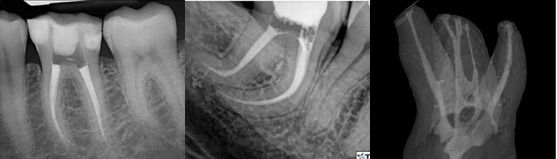

Root Canal Treatment

A root canal treatment is a dental procedure of choice when an individual wants to save or retain the tooth because an infection has reached the core of the tooth where there are nerves and blood vessels that supply nourishment to the tooth. This usually happens when your decay has spread deep within and caused irreversible damage to the structures or causes the active spread of infection. Prices of doing a root canal treatment vary because root canal systems vary in their shape, size, direction or complexity. The more complex a root canal system is, not only do we need more non-reusable instruments, but it also requires more time and effort.